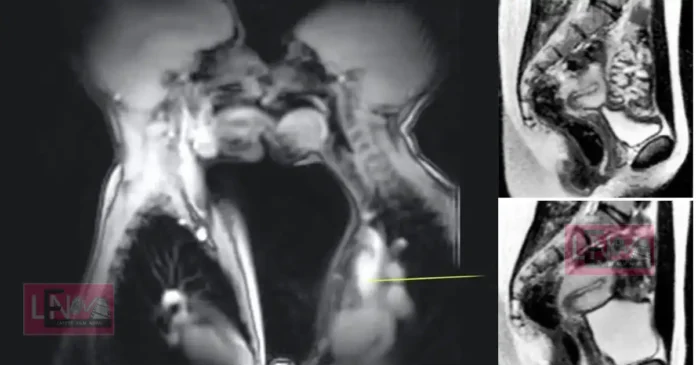

എം.ആർ.ഐ മെഷീനുകൾ ആദ്യമായി ഉപയോഗിച്ചു തുടങ്ങിയ കാലമായിരുന്നു അത്. അതുകൊണ്ടുതന്നെ വ്യക്തമായ ചിത്രങ്ങൾ ലഭിക്കാൻ ഏറെ സമയമെടുത്തിരുന്നു. കൺട്രോൾ റൂമിൽ നിന്നും നിർദ്ദേശം ലഭിക്കുന്നതുവരെ ചിലപ്പോൾ മിനിറ്റുകളോളം ഒരേ പൊസിഷനിൽ തന്നെ ദമ്പതികൾക്ക് തുടരേണ്ടി വന്നിട്ടുണ്ട്. വളരെ ഇടുങ്ങിയ, വെറും 50 സെന്റീമീറ്റർ മാത്രം വ്യാസമുള്ള ആ ട്യൂബിനുള്ളിൽ സാധാരണ ഗതിയിലുള്ള (missionary) പൊസിഷനുകൾ സാധ്യമായിരുന്നില്ല. അതിനാൽ വശങ്ങളിലേക്ക് ചരിഞ്ഞുകിടന്നുള്ള (spooning) രീതിയാണ് ഇവർ തിരഞ്ഞെടുത്തത്.

ലോകത്തെ അമ്പരപ്പിച്ച കണ്ടെത്തലുകൾ

1999-ൽ പ്രശസ്തമായ ബ്രിട്ടീഷ് മെഡിക്കൽ ജേർണലിൽ (BMJ) ഈ പഠനത്തിന്റെ ഫലങ്ങൾ പ്രസിദ്ധീകരിച്ചു. വൈദ്യശാസ്ത്രരംഗത്ത് വലിയൊരു തിരുത്തലായിരുന്നു ആ പഠനം. ഡാവിഞ്ചിയുടെ കാലം മുതൽ വിശ്വസിച്ചുപോന്നിരുന്ന പല ധാരണകളും ഈ എം.ആർ.ഐ ചിത്രങ്ങൾ തിരുത്തിക്കുറിച്ചു. ലൈംഗികബന്ധ സമയത്ത് പുരുഷലിംഗം ഒരു ‘ബൂമറാങ്ങിന്റെ’ (Boomerang) ആകൃതിയിലേക്ക് വളയുന്നുണ്ടെന്നും, അല്ലാതെ അത് നേരായ സിലിണ്ടർ ആകൃതിയിലല്ല നിലകൊള്ളുന്നതെന്നും എം.ആർ.ഐ സ്കാനിംഗിലൂടെ തെളിയിക്കപ്പെട്ടു. ഇത് പുരുഷന് വേദനയുണ്ടാക്കാതെ തന്നെ സ്ത്രീയുടെ യോനിയുടെ ആകൃതിക്കനുസരിച്ച് വളയാൻ സഹായിക്കുന്നു. കൂടാതെ, ലൈംഗിക ഉത്തേജന സമയത്ത് സ്ത്രീകളുടെ ഗർഭപാത്രത്തിന്റെ വലുപ്പം വർദ്ധിക്കുന്നില്ല എന്ന പുതിയ വിവരവും ഈ പഠനം ശാസ്ത്രലോകത്തിന് നൽകി.